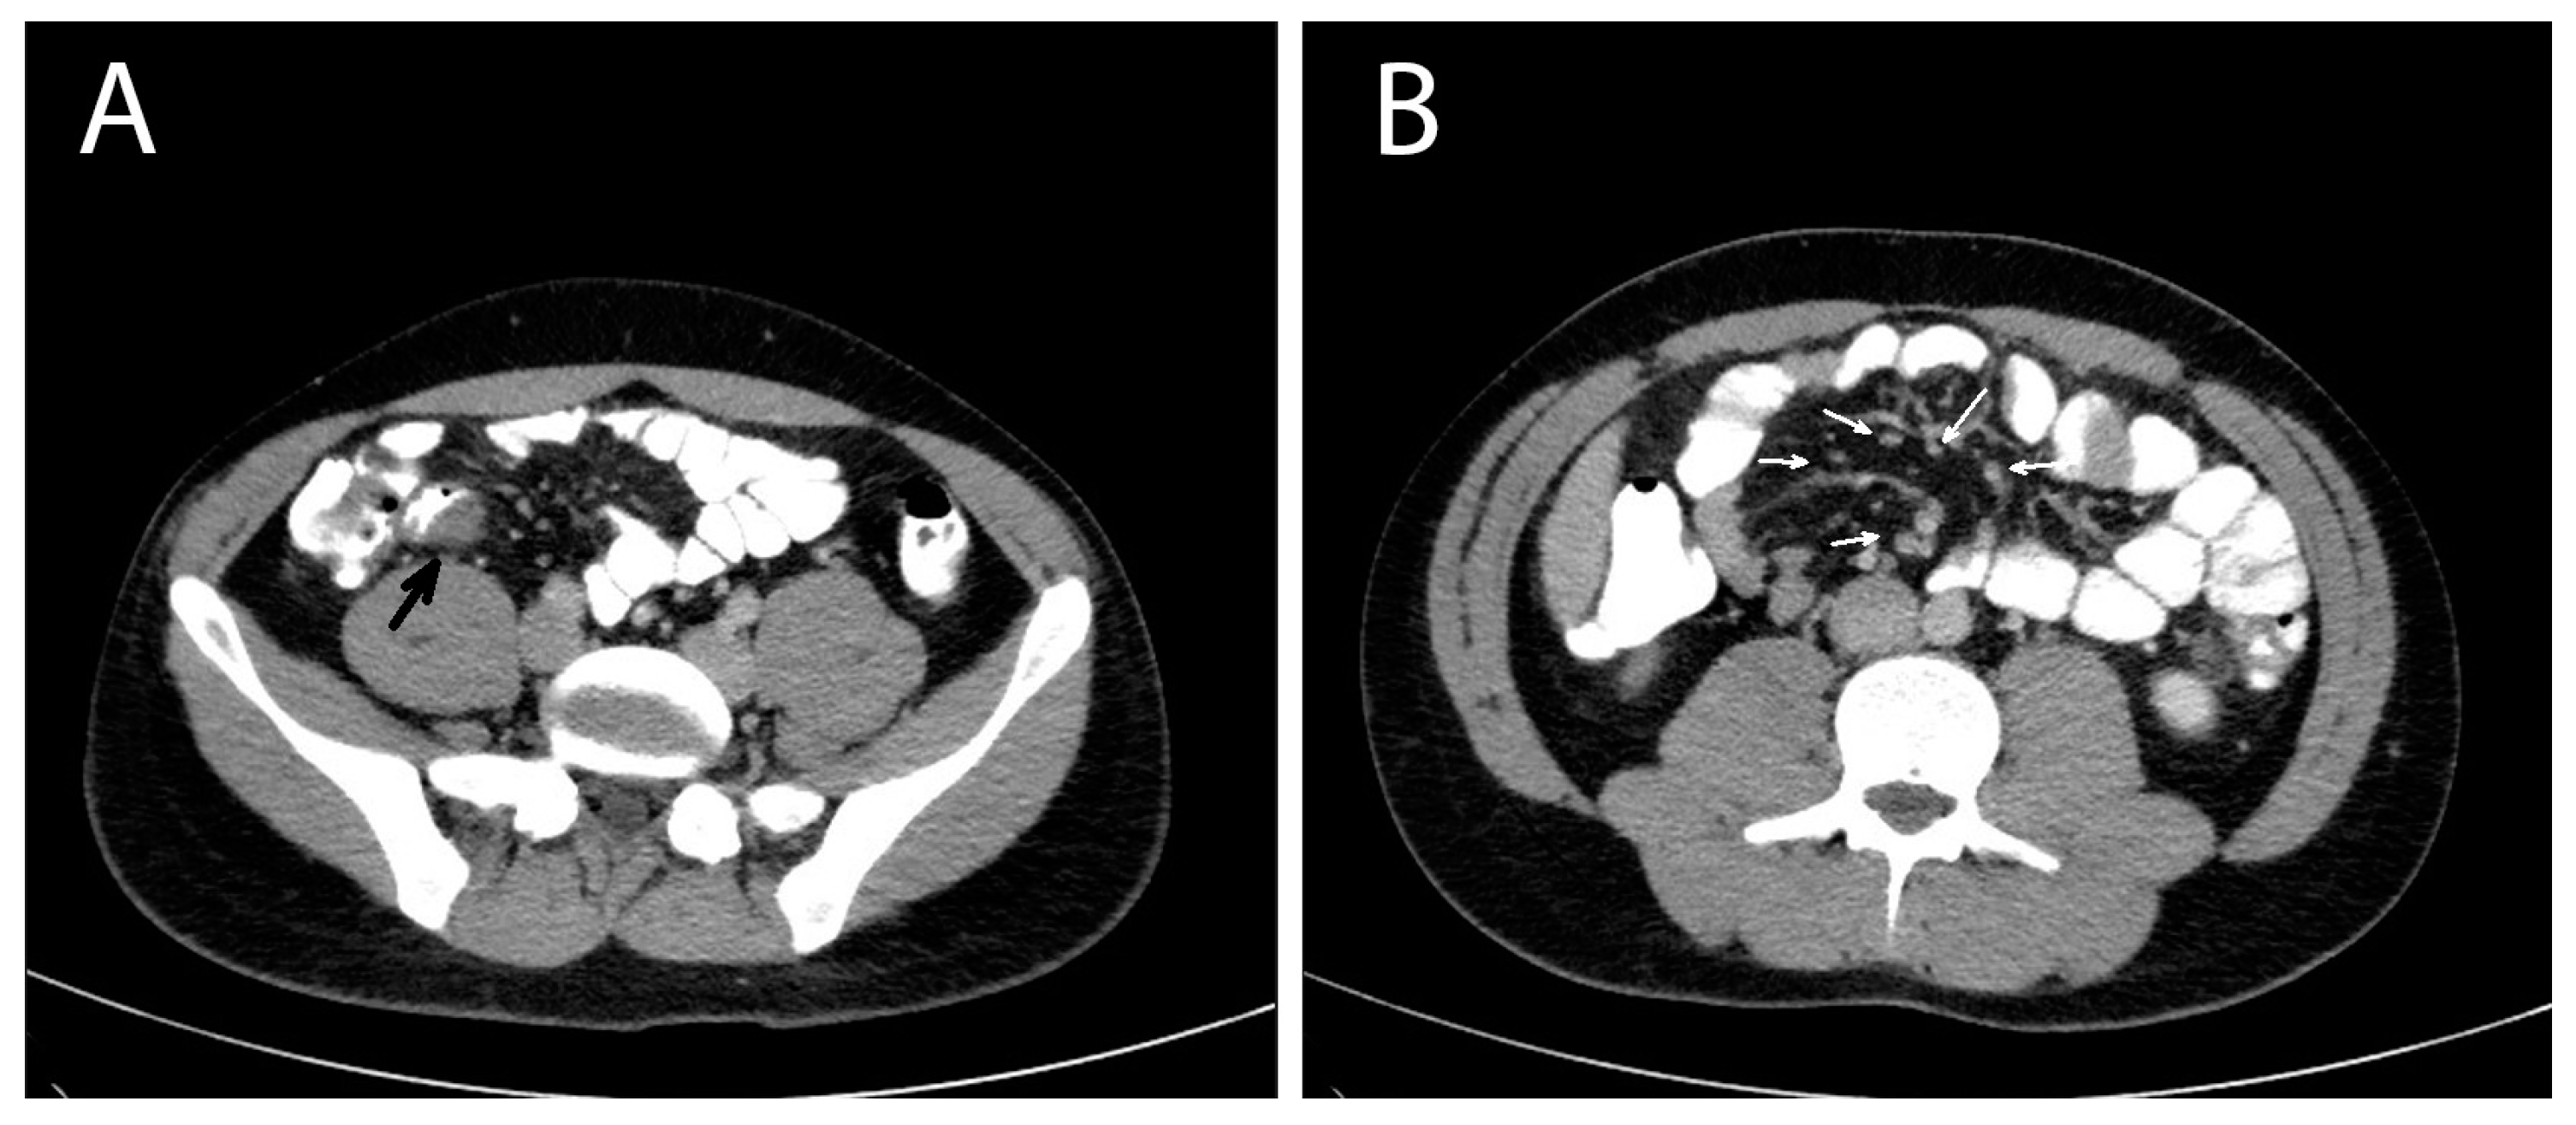

A contrast-enhanced computed tomography (CT) of the abdomen was performed the next day that showed multiple masses with soft tissue densities at the gastrocolic ligament (max ~1.1 cm), the left part of greater omentum (max ~1.5 cm), right paracolic gutter (max ~0.7 cm) and the left pararenal space (max ~1.7 cm), with multiple enlarged mesenteric lymph nodes along the ileocolic vessels (max ~1 cm), and at the aortic hiatus of the diaphragm (max ~1.2 cm). A thickening at the wall of the distal ileum right before the ileocolic junction was also depicted (Figure 1). The CT findings suggested a neoplastic disease and endoscopy of the upper and lower gastrointestinal tract was decided on. The oesophagogastroscopy was normal and a colonoscopy revealed a mild oedema of the mucosa of the distal ileum and a sessile polyp of the distal sigmoid. The investigation was completed with a computed tomography (CT) scan of the thorax, which was normal, and a contrast-enhanced MRI of the abdomen that depicted the same nodules and enlarged lymph nodes showed in the CT scan, in addition to a small quantity of pelvic fluid (ascites). During the investigation, the patient remained afebrile and hemodynamically stable, with, however, persistent abdominal symptoms and signs.

Figure 1. Abdomen contrast-enhanced MRI of a patient with invasive intestinal anisakiosis. (A): Distal ileum lesion (black arrow). (B): Multiple lymph nodes along ileocolic vessels (white arrows).